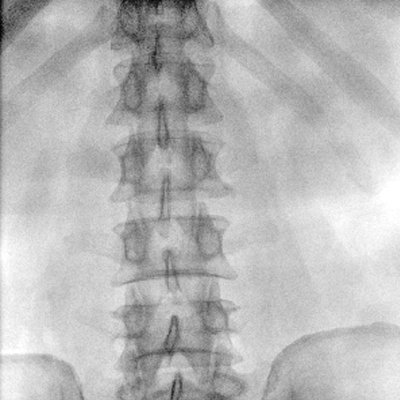

大尺寸動態平板探測器,高DQE、低噪聲、圖像清晰。采用多分辨率圖像增強處理技術,不同部位不同圖像處理算法,滿足客戶多樣化的需求。

采用智能變頻脈沖透視技術,優化圖像質量的同時降低輻射劑量,呵護醫患健康